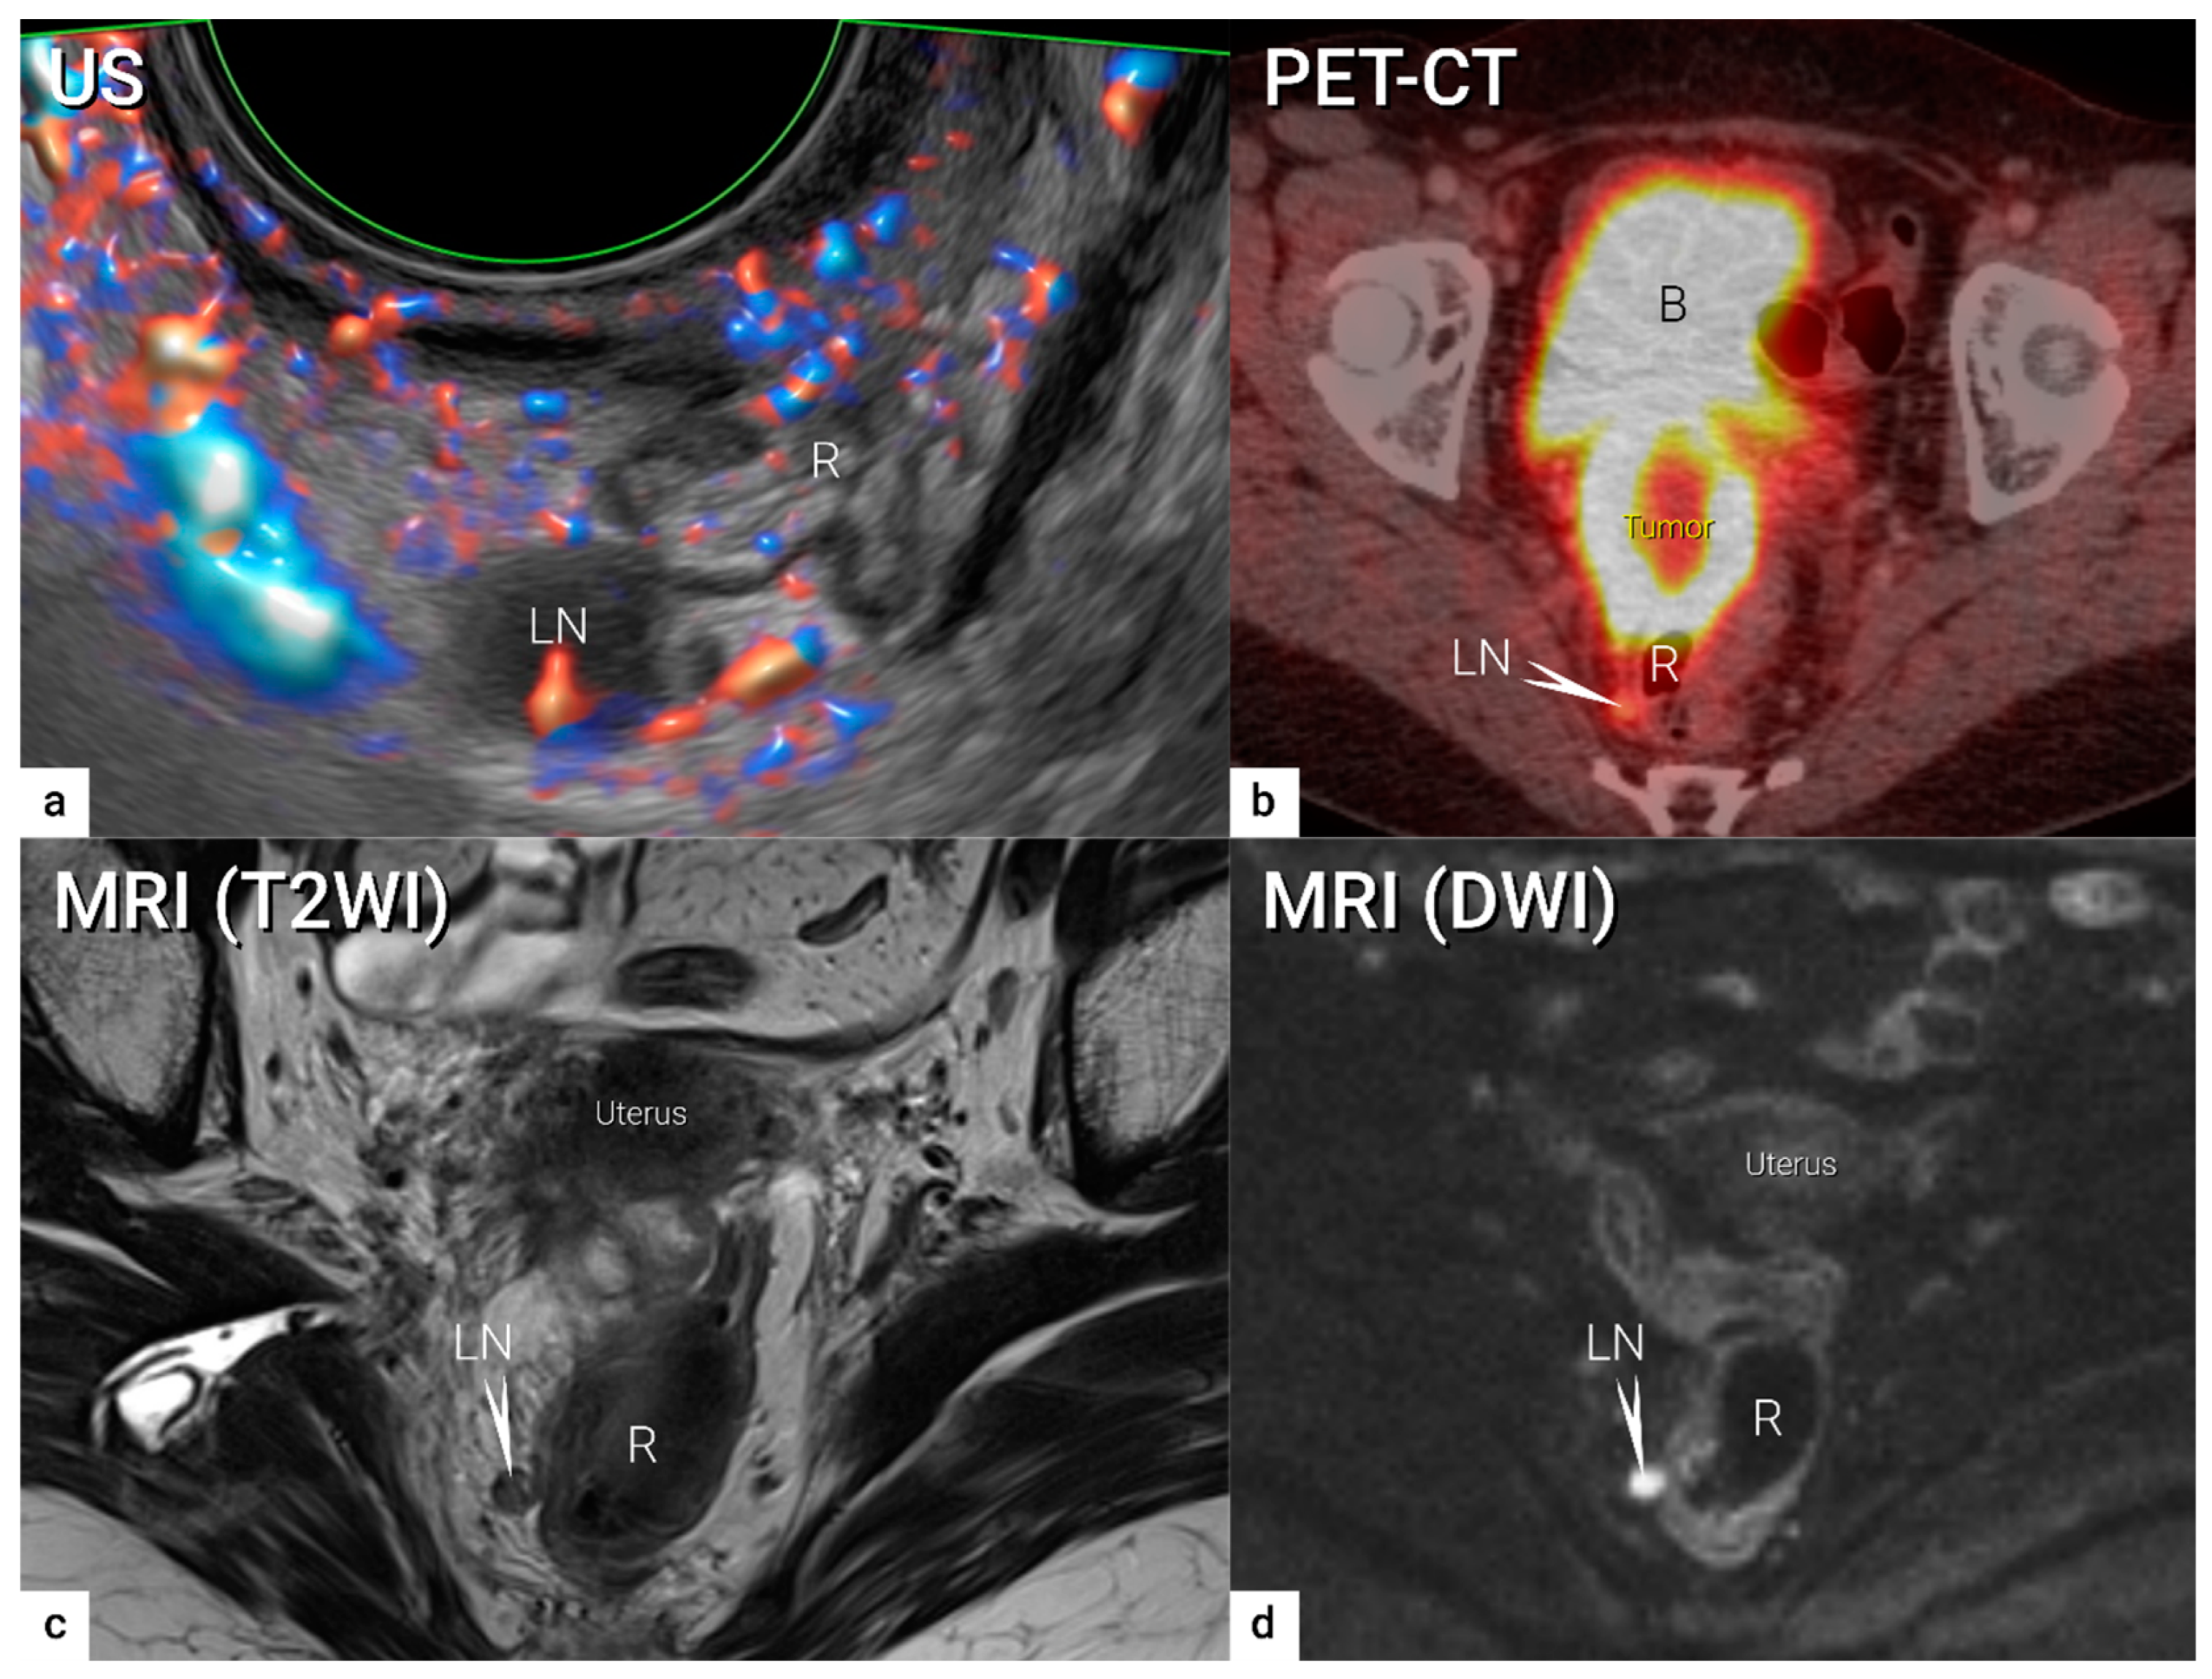

| N1 | IIIC1 | Regional lymph node metastasis to pelvic lymph nodes only | US: hypoechogenic rounded lymph node without preservation of typical architecture (loss of the nodal core-sign), inhomogeneous echogenicity due to cystic necrosis and calcifications, capsular interruption, grouping of metastatic lymph nodes and others. Hilar flow may still be preserved in a partial nodal involvement with or without transcapsular vascularisation (vessels penetrating the cortex from outside), the latter are usually found in an advanced stage of infiltration. MRI: lymph nodes with maximum transverse diameter >10 mm; capsule irregularity, rounded (as opposed to oval) shape, inhomogeneous signal with signs of necrosis on T2W images (MRI), restricted diffusion (DWI) or increased FDG-avidity (PET-CT) |